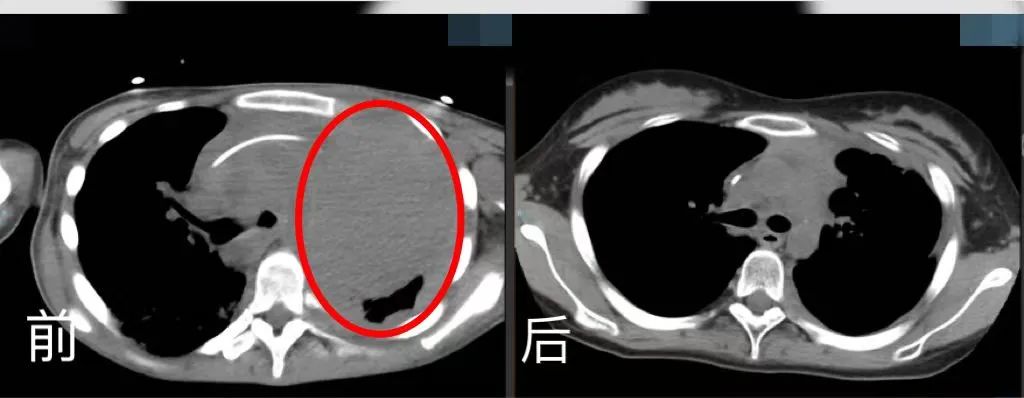

5月4日,對于17歲的少女小玉(化名)不僅是一個節日,也是她重生的日子。手捧著鮮花、笑起來甜甜的她,原本胸腔幾乎三分之二被腫瘤占滿,此刻體內腫瘤幾乎消失無形,達到臨床完全緩解狀態。

胸腔CT前后對比。四川省腫瘤醫院供圖